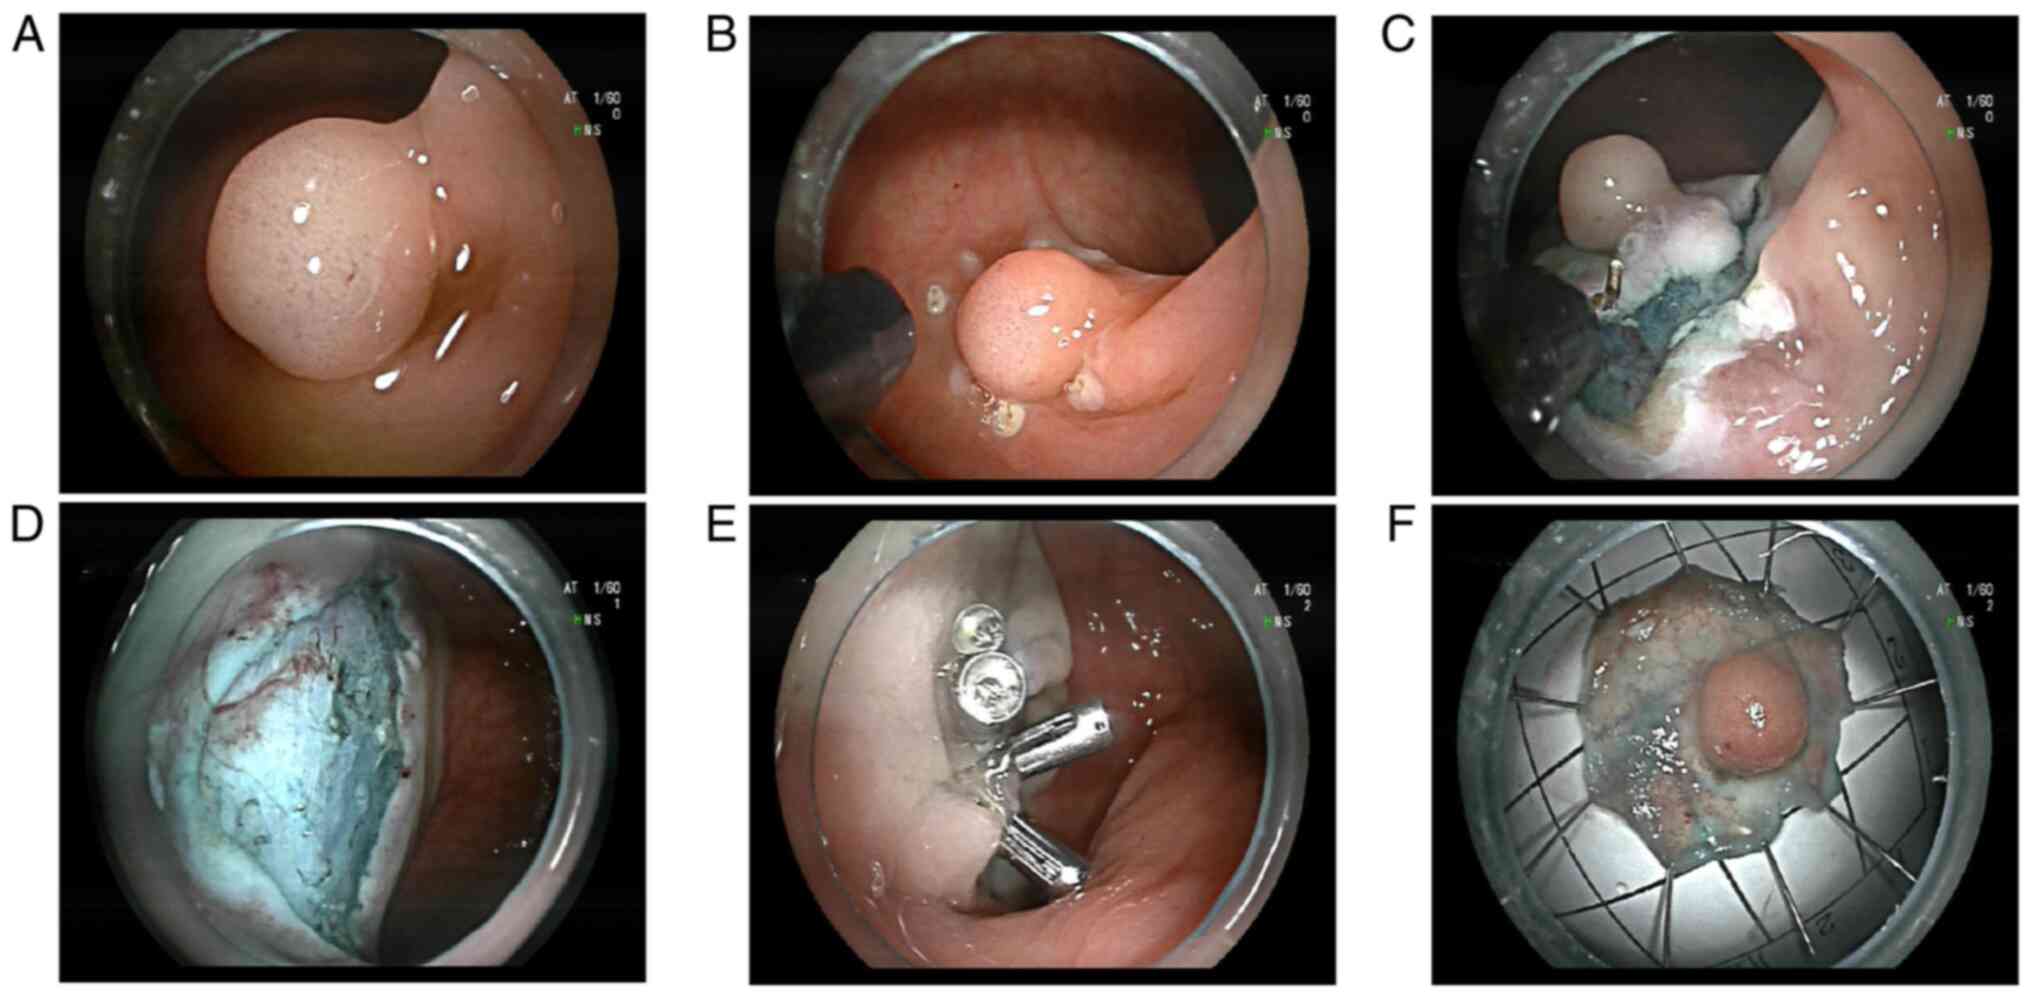

Figure 2

(A) Rectal submucosal tumor. (B) Submucosal tumor of the rectum marked with a hook knife. (C) Submucosal tumor of the rectum cut and peeled with the hook knife edge. (D) Wound surface after ESD resection. (E) Multiple titanium clips closed the wound. (F) The excised specimen area was ~1.8x1.8 cm and the tumor size was 0.6x0.8 cm.